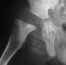

- 2 month Office Follow Up: Rt hip Xray: progressive destruction of capital

femoral epiphysis, cystic changes in metaphysis consistent with AVN.

This case is an example of untreated septic arthritis which caused avascular

necrosis of the proximal femur. The primary cause of this is undrained

septic hip. Repeated aspiration is not adequect treatment of a septic hip.